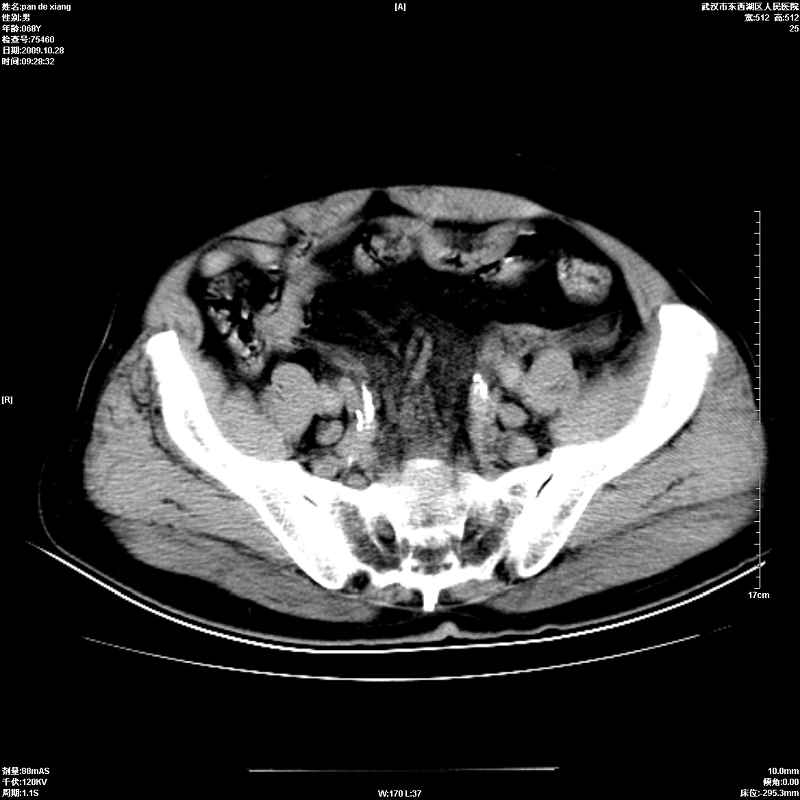

以下是引用杀毒软件在2009-10-28 20:41:00的发言:[br]结合临床考虑---白血病双肾改变或淋巴瘤。

以下是引用zxl51642在2009-10-29 9:59:00的发言:[br]结合临床“单克隆免疫球蛋白血症”,考虑双肾为继发损害并肾功能不全(尿中大量igg及少量iga、igm等大分子免疫球蛋白滤出所致继发损害),椎前软组织肿块为髓外造血。与浆细胞瘤有区别,平扫时有战友说的很清楚。